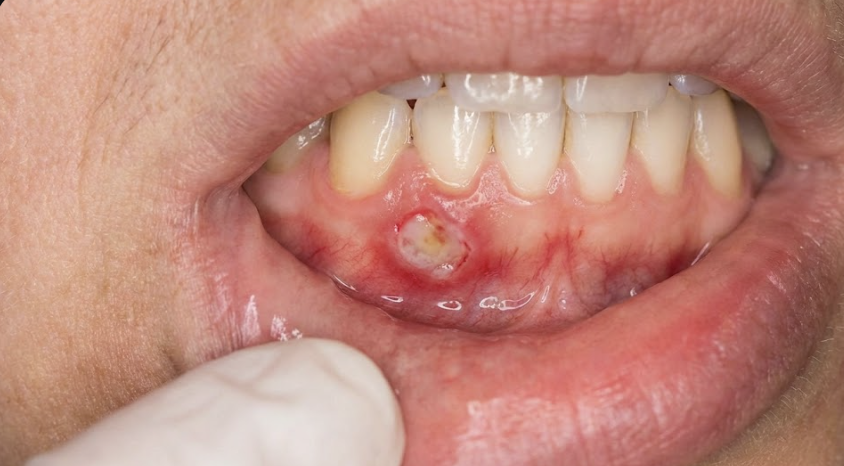

歯茎にできる口内炎とは?

口内炎というと、頬の内側や舌にできるイメージを持たれる方が多いですが、

歯茎(歯肉)にも口内炎はできます。

歯茎の口内炎は、

白くえぐれたように見える

周囲が赤く腫れる

触れると強く痛む

歯磨きや食事がつらい

といった特徴があります。

特に歯茎は歯や被せ物、矯正装置などと接触しやすいため、

刺激が原因で治りにくく、再発しやすいのが特徴です。